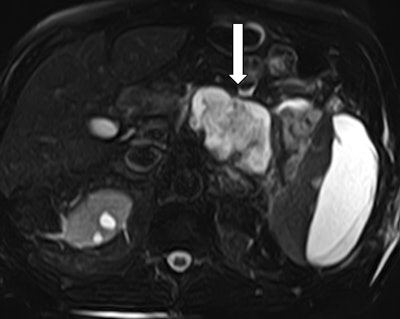

A provisional diagnosis of systemic inflammatory response syndrome (SIRS) was made, after which blood cultures were obtained, and broad-spectrum antibiotics were started and then stopped in 24 hours due to negative blood cultures. MR cholangiopancreatography (MRCP) of the abdomen confirmed a necrotic collection involving most of the pancreatic body and tail (figure 4). The pancreatic duct was encompassed by the collection and difficult to appreciate.

Figure 4: MRCP confirms an acute necrotic collection. T2-weighted sequence of an abdominal MRI demonstrates involvement of the pancreatic body and tail. The pancreatic duct is obliterated by the collection and cannot be appreciated.Over the course of the following week, our patient's WBCs and lipase normalized, and he was discharged home with a two-week follow-up CT of the abdomen.